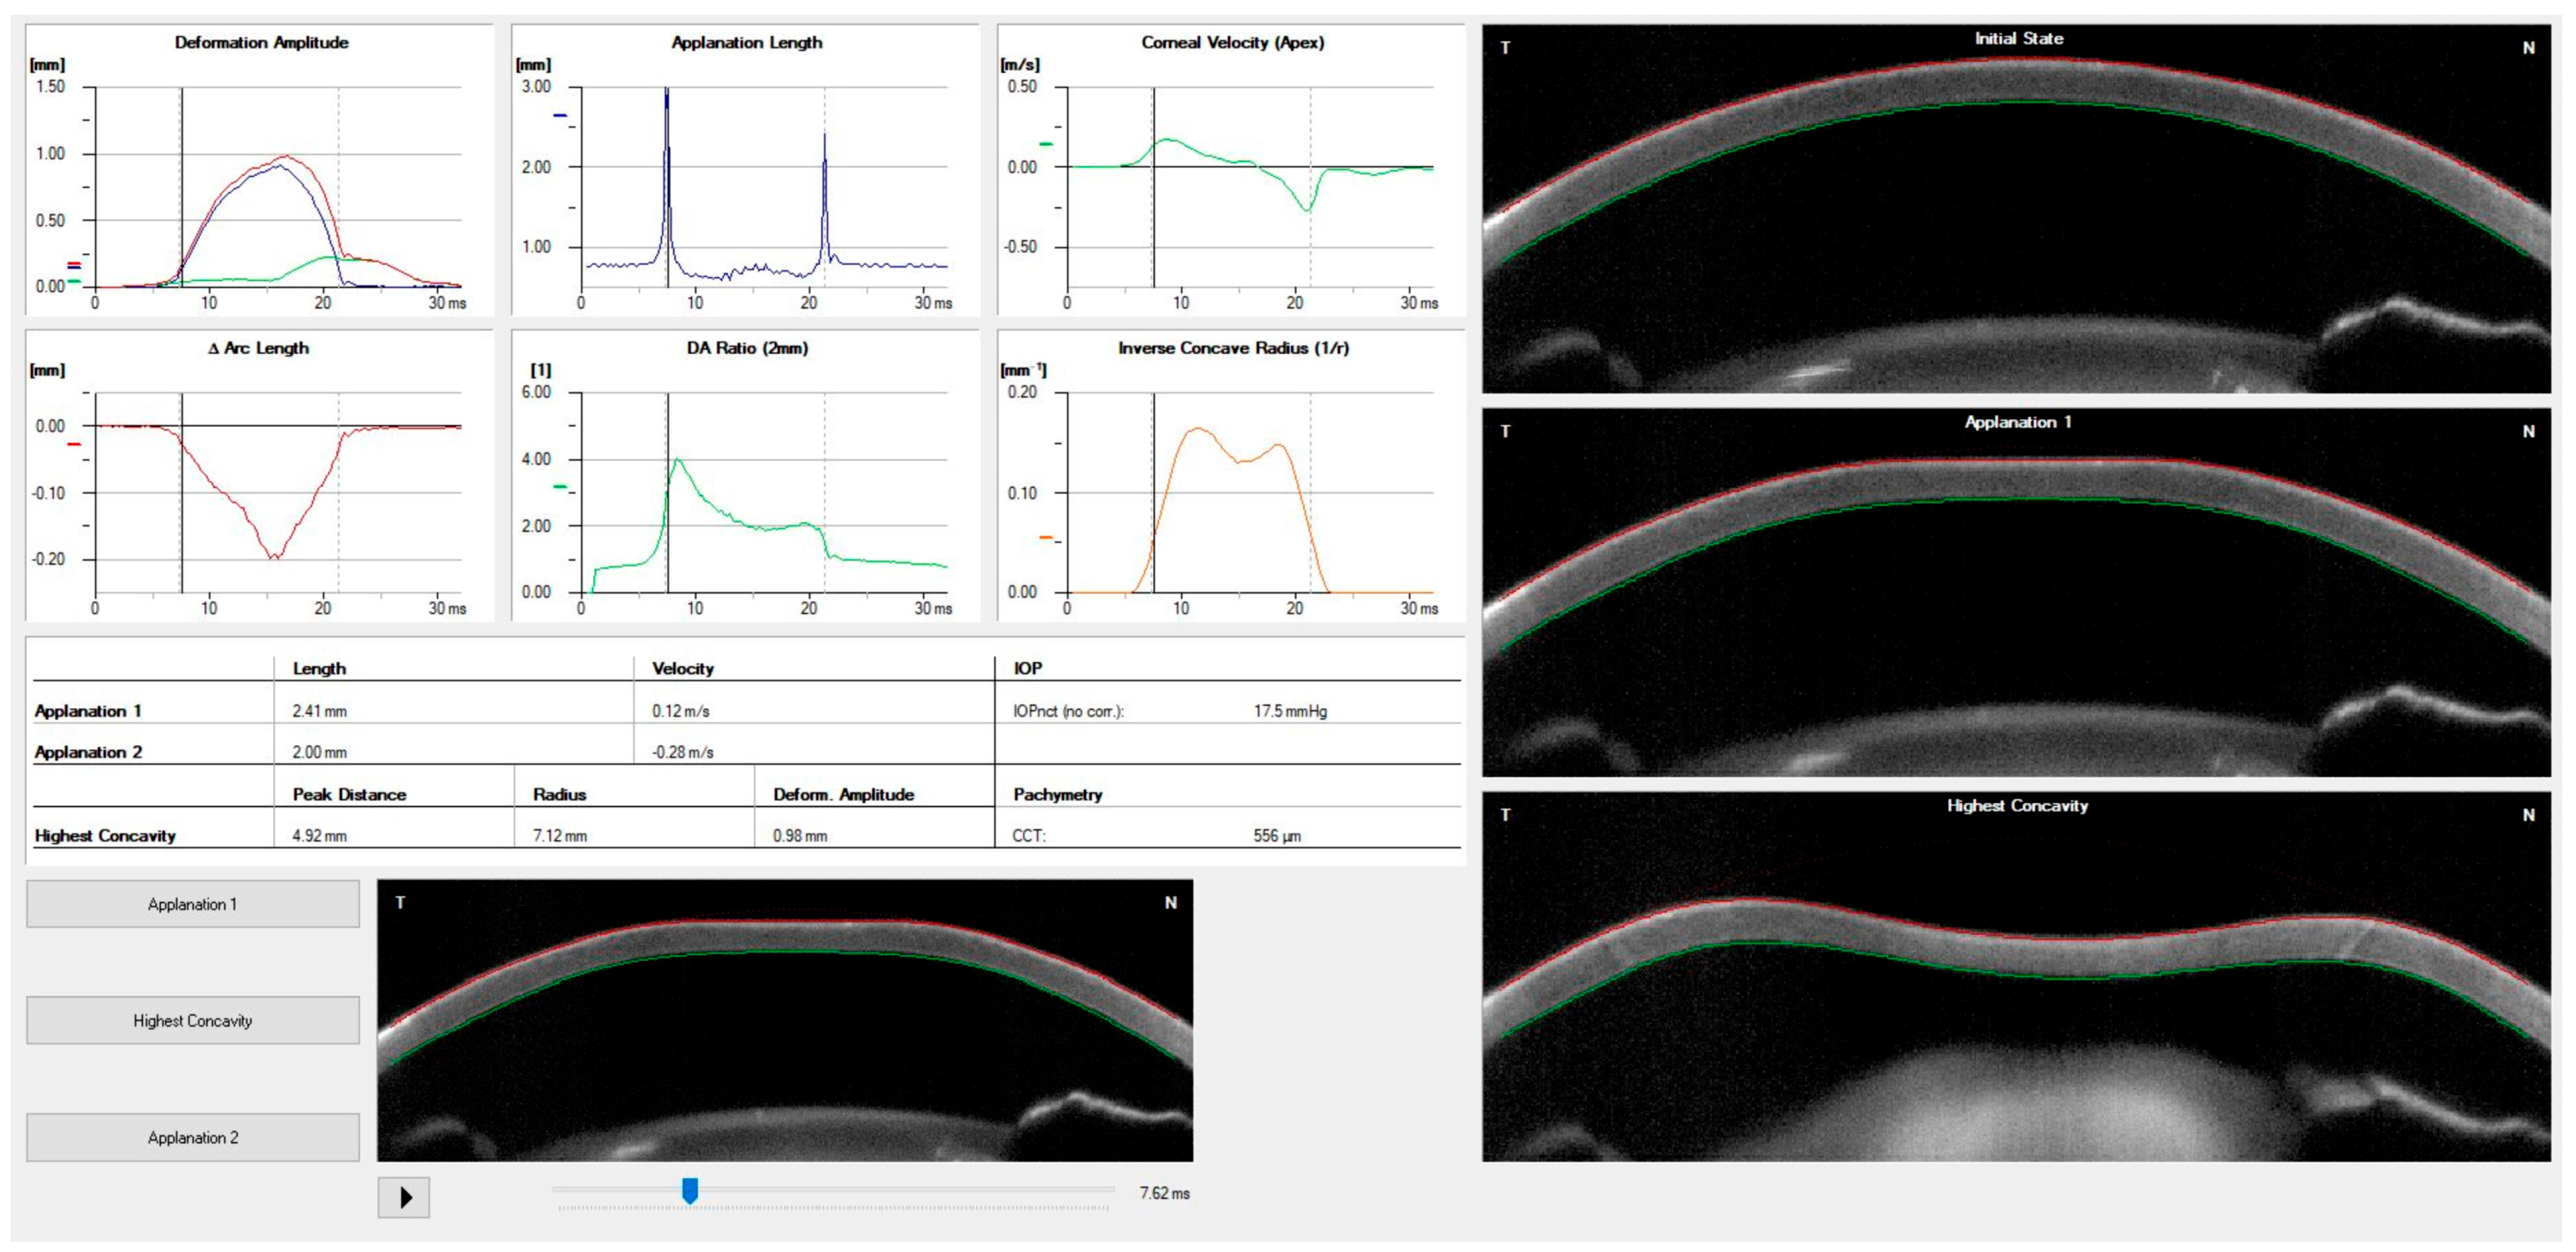

| Corvis ST Parameter | Definition |

|---|---|

| 1st Applanation | The first applanation of the cornea during the air puff (in ms). The length of the applanation at this moment appears in parenthesis (in mm). |

| Highest Concavity | The instant that the cornea assumes its maximum concavity during the air puff (in ms). The length of the distance between the two peaks of the cornea at this moment appears in parenthesis (in mm). |

| 2nd Applanation | The second applanation of the cornea during the air puff (in milliseconds). The length of the applanation at this moment appears in parenthesis (in mm). |

| Maximum Deformation | The amount (in mm) of the maximum corneal deformation during the air puff. |

| Wing Distance | The length of the distance between the two peaks of the cornea at this instant (in mm). |

| Maximum Velocity (in) | The maximum velocity during the ingoing phase (in m/s). |

| Maximum Velocity | The maximum velocity during the outgoing phase (in m/s). |

| Curvature Radius Normal | The cornea in its natural state has a radius of curvature (in mm). |

| Curvature Radius HC | The corneal radius of curvature at the time of maximum concavity during the air puff (in mm). |

| Cornea Thickness | Measurement of the corneal thickness (in mm). |

| IOP | Measurement of the intraocular pressure (in mmHg). |

| bIOP | Biomechanically-corrected IOP. |

| DA ratio Max (Deformation amplitude ratio max. 2 mm) | Ratio between the deformation amplitude at the apex and the average deformation amplitude measured at 2 mm from the center. |

| ARth (Ambrósio’s relational thickness to the horizontal profile) | Describes the thickness profile in the temporal-nasal direction and is defined as corneal thickness from thinnest to pachymetric progression. |

| SP-A1(Stiffness parameter at A1) | Describes corneal stiffness as defined by resultant pressure (Pr) divided by deflection amplitude at A1. |

| SP-HC | Corneal stiffness at the highest concavity point. |

| TBI (Tomographic biomechanical index) | Index that combines tomographic and biomechanical data for keratoconus detection. |

| BGF (Biomechanical Glaucoma factor) | Independent risk indicator for normal tension glaucoma. |

| SSI (Stress-strain index) | Index that indicates the position of the stress-strain curves. Less dependent on corneal thickness and IOP. |

| CBI (Corvis biomechanical index) | Overall biomechanical index for keratoconus detection. |

| Whole eye movement (WEM) | The entire globe’s movement after the cornea passes its limits during the jet air pulse is resisted by the orbital structures. |

| Deformation Amplitude (DA) | The movement of the corneal deformation from the apex to the highest concavity. |

| Deflection amplitude (DeflA) | The difference between the DA and the WEM. |

| HC dArc length | Change in arc length during the highest concavity moment from the initial state, in a defined 7-mm zone. |

| HC deflection length | Length of the flattened cornea at its highest concavity. |